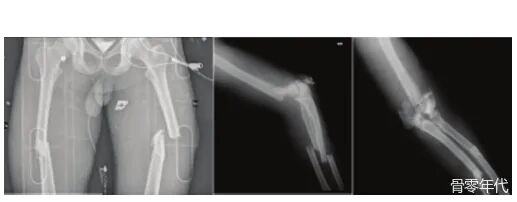

影像学表现